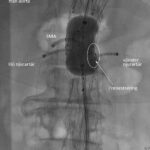

- Sterildrapering av patient och utrustning görs lämpligen tillsammans med ass. röntgenssk. [Bild 1][Bild 2][Bild 3]